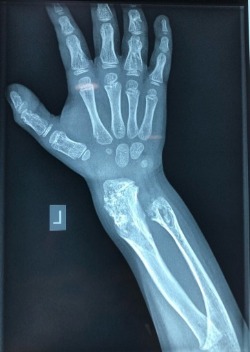

Νόσος του Όλιερ

Οι εικόνες απεικονίζουν ένα περιστατικό με την Νόσο του Όλιερ, όπου παρουσίαζε κοντύτερο αριστερό άκρο. Χειρουργήθηκε από τον Δρ. Ζένιο με την χρήση εξωτερικής οστεοσύνθεσης.

Προ-εγχειρητικά

Εξωτερική

οστεοσύνθεση

Μετ-εγχειρητικά